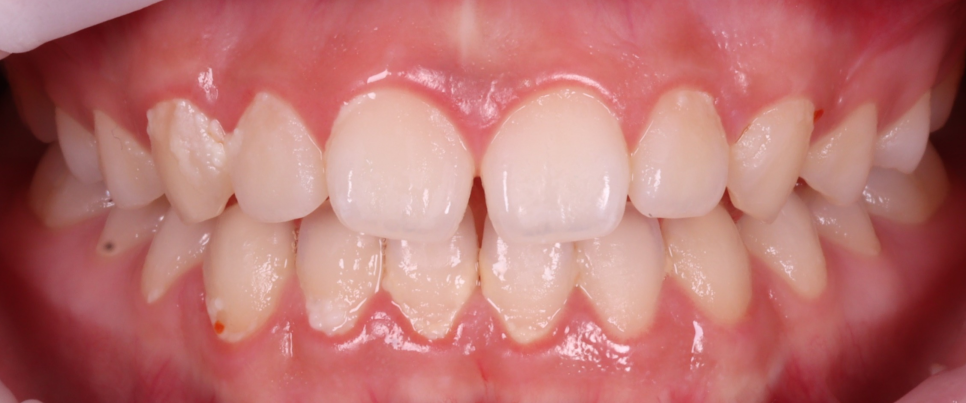

촬영 : 251030

길이를 연장할 경우 턱을 내밀었을 때, 아랫니가 윗니와 닿아서 아랫니가 닿지 않도록 조정해야 합니다.

환자분은 우선 벌어진 것만 원하셨어요.

두 치아의 길이와 폭 비율을 맞추고 웃을 때 자연광 아래에서도 자연스럽도록 투명도와 형태를 조정하기로 했습니다.